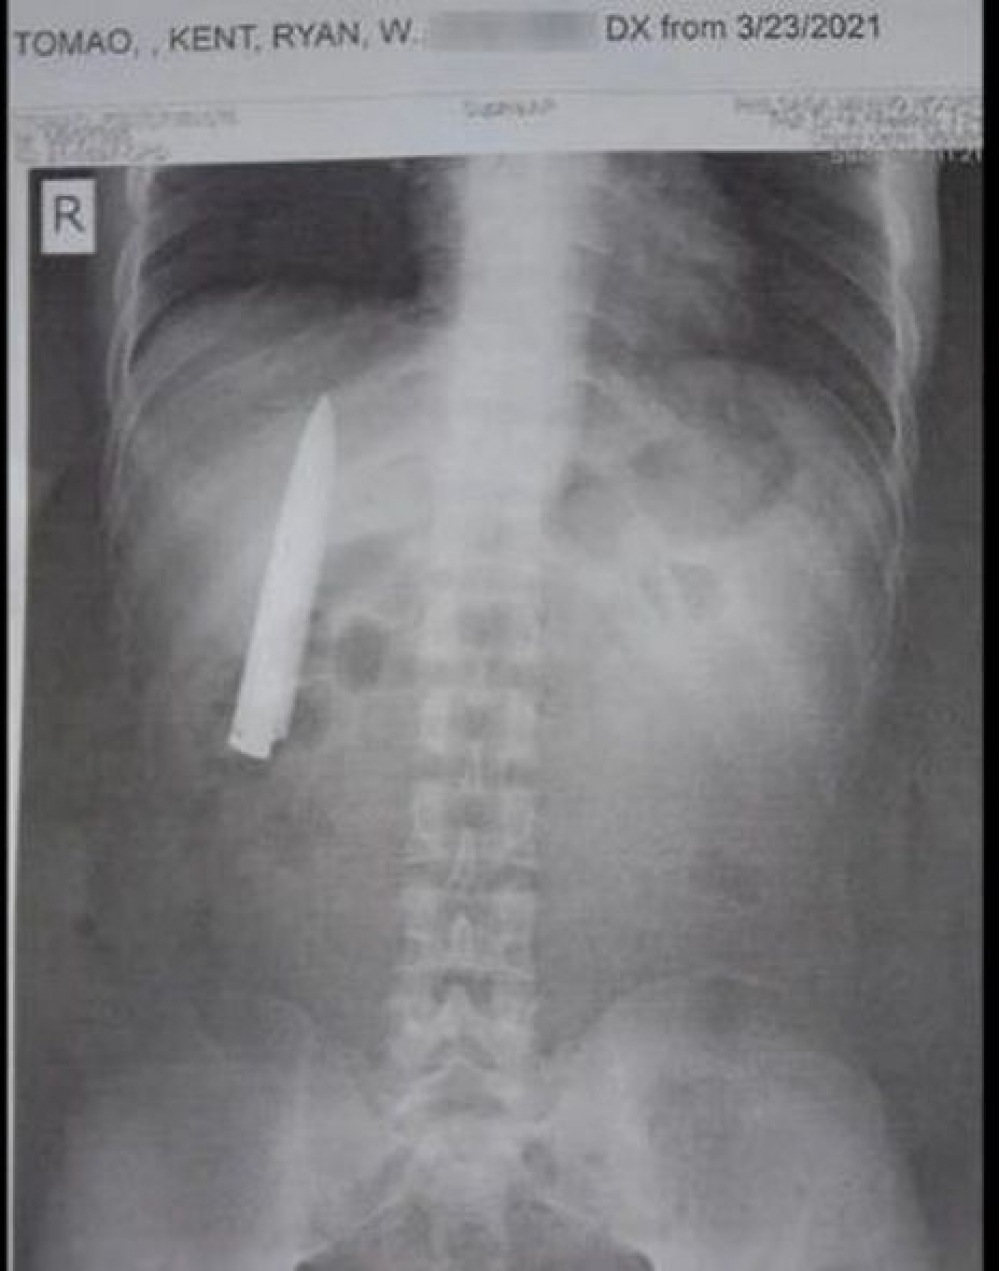

Sinəsinə saplanan bıçaqdan bir il xəbəri olmadı

Filippin sakini xuliqanların hücumundan sonra bir il bədənində bıçaq gəzdirib, ancaq bundan xəbəri olmayıb.

"İki sahil" xəbər verir ki, bu barədə “Cocontus” xəbər yayıb. Bildirilir ki, 25 yaşlı Kent Rayan Tomao 2020-ci ildə Filippinin Kidapavan şəhərinə gəzməyə gedərkən bir qrup yeniyetmənin hücumuna məruz qalıb və bıçaqlanıb. Dövlət xəstəxanasında həkim müayinə etdikdən sonra yaranı yüngül sayıb və rentgenə ehtiyac duymadan tikiş atıb.

Tomaonun sözlərinə görə, soyuq havalarda yarası incidib, ancaq bunun səbəbini bu yaxınlarda döş qəfəsinin rentgeni zamanı öyrənib. Şəkildə ağciyərlərin yanında bıçağın ülgücü aydın görünür. Gənc yenidən Kidapavan şəhərinə qayıdaraq, əməliyyat üçün elə həmin xəstəxanaya müraciət etmək istəyir. Bununla belə o, nə həkimləri, nə də xəstəxananı şikayət etmək fikrində deyil.